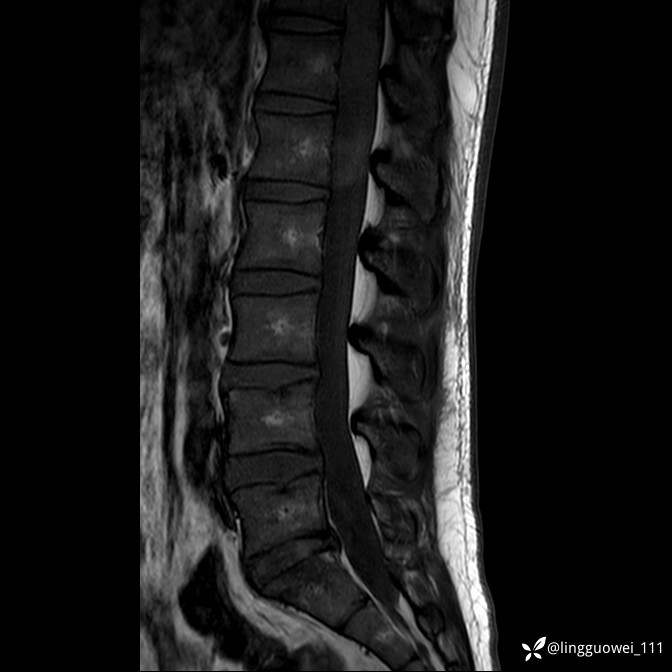

男,38岁,反复腰痛伴双腹股沟区痹痛半年,加重1月。

腰椎MR,注意脊髓异常信号,与伪影鉴别,一不小心就会漏诊

T2WI T2WI+FS